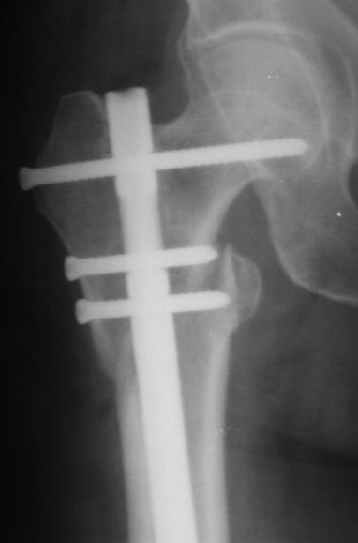

Я пошел на операцию имея стерильным и обычный бедренный гвоздь ChM и реконструктивный.

Когда открыто убрали DHS встали перед выбором, что ставить? Так, как это был подвертельный перелом - поперечная линия на уровне малого вертела то поставили обычный бедренный гвозь и один прокс блокирующий винт, который затянули компрессирующей заглушкой.

В частности, на проксимальном конце сделано еще одно дополнительное статическое отверстие. Можно ввести в проксимальном отделе 4 винта, из них 3 статические (2 в круглые отверстия и 1 по нижнему краю овального). Картинки в приложении. На дистальном конце стержня тоже кое-что улучшено. Спрашивайте в аптеках, как говорится. Выпускается предприятием "ЦИТО" (Москва), то есть это малобюджетное решение.

Конечно, мы не синтезируем остеопорозые вертельные переломы согласно прилагаемому примеру, винты 6 мм вырежутся. Но у более молодых при хорошем качестве кости такие или подобные гвозди с поперечным расположением винтов вполне применимы для меж- и подвертельных переломов.

Картинка красивая, но на мой взгляд, не совсем оптимальная: Слишком медиально введён стержень - риск аваскулярного некроза головки бедра.

Это было года 2,5 назад, мы тогда еще уточняли возможности шинирования с угловой стабильностью гвоздем с поперечным расположением винтов при переломах проксимального отдела бедра. Пациенту не пришлось приобретать намного более дорогой рекон или проксимальный гвоздь. В приложении еще несколько примеров применения того гвоздя при высоких переломах бедра, в том числе с более латеральной точкой входа. Гвоздь изгибаем для этого.